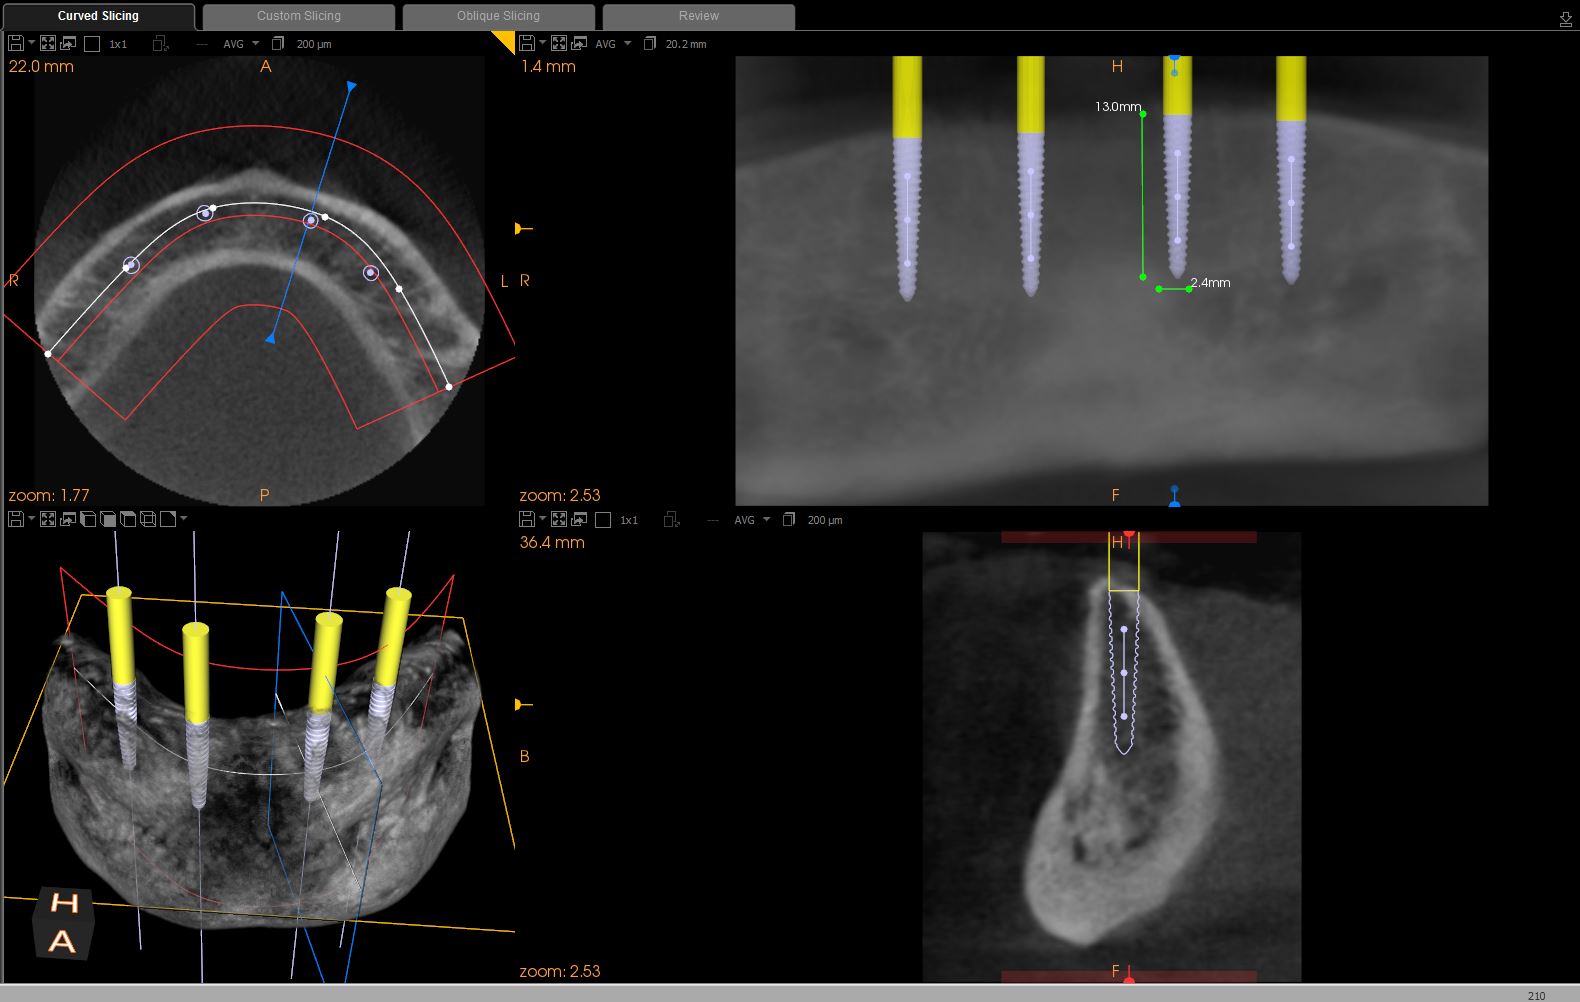

A sterile operating environment was established. Prior to administering anesthesia the location of the mental foramen and the exiting neurovascular bundle was established by palpating the facial aspect of the mandible; this procedure was performed in conjunction with the cross-sectional CBCT imaging. If this technique is inadequate, a radiographic splint can be used to further verify the position of the mental foramen; often, a patient’s existing mandibular denture can be modified for this purpose. A surgical marker was used to mark the proposed implant positions with at least 3-mm inter-implant spacing (Figure 2). Establishing the position of the mental nerve prior to administering local anesthesia is necessary, because the injection site will become filled with anesthetic solution, and/or submucosal hematoma will interfere with accurate palpation. Sufficient pain control was achieved via infiltration of local anesthetic in the area of the mental foramen as well as along the crest of the anterior mandible. Care was taken to minimize the patient’s exposure to epinephrine.

Fig 2. Preoperative view of mandible with proposed implant locations marked.

Figure 2